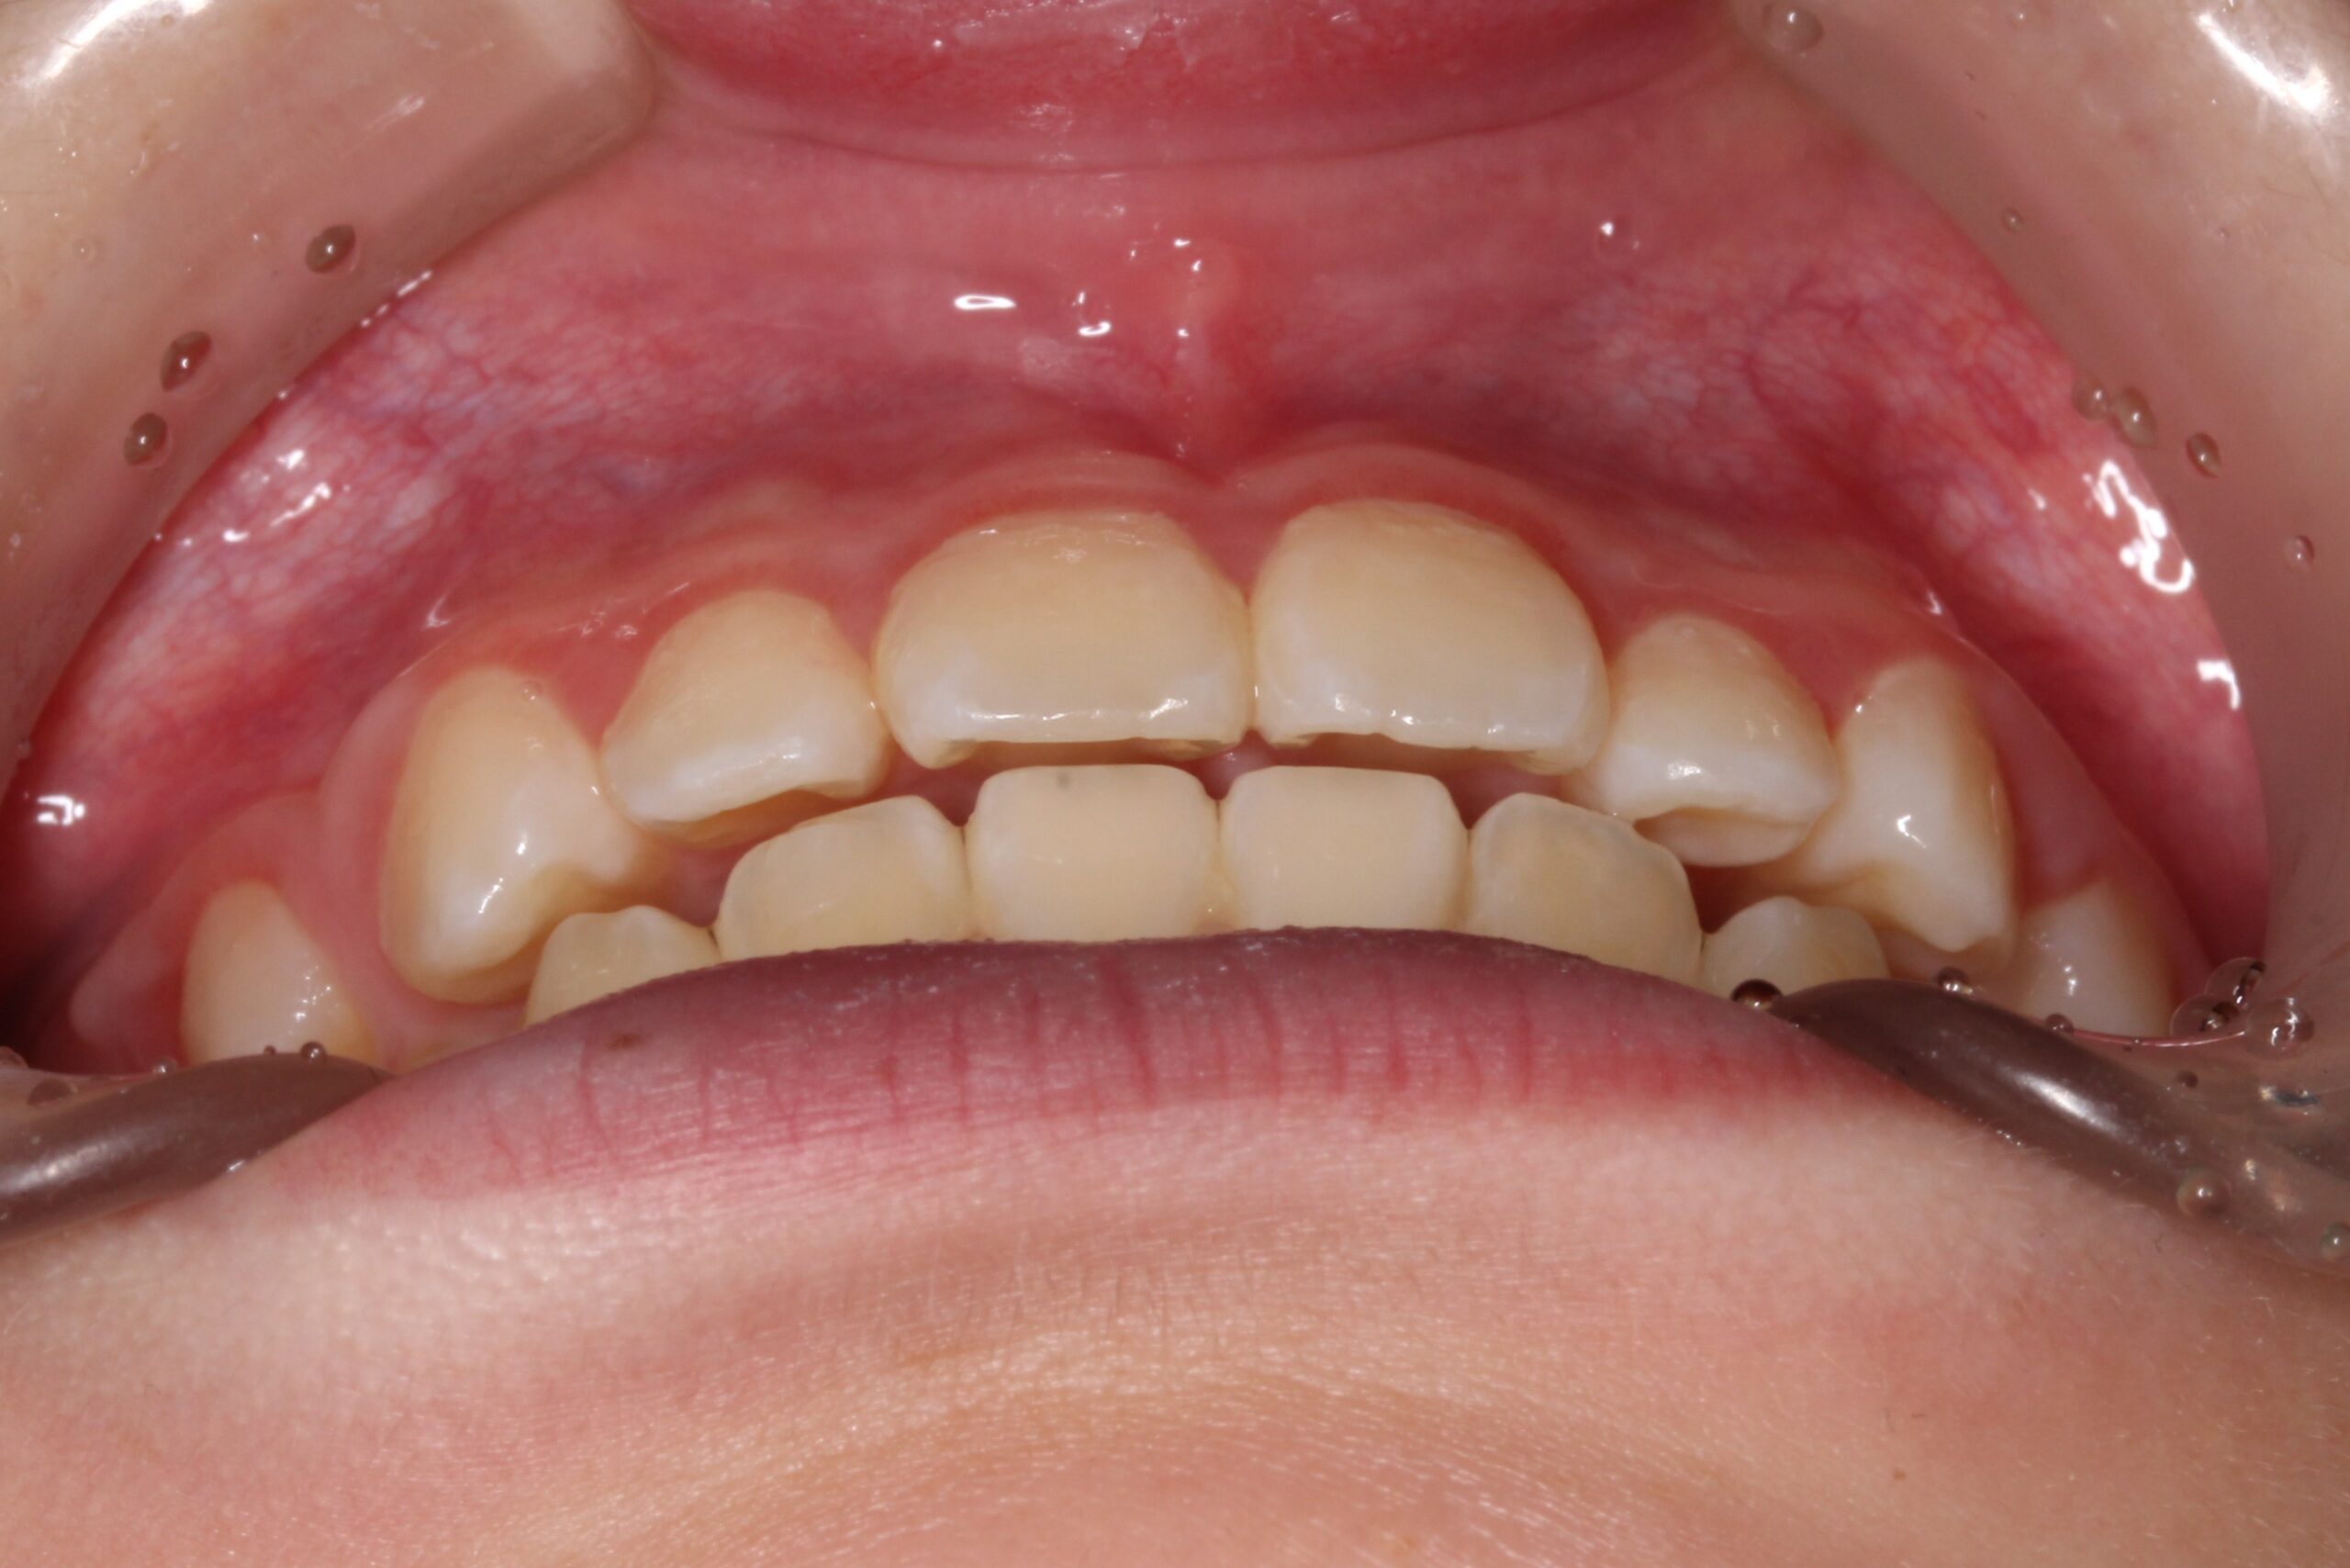

矯正術前:正面

矯正術後:正面